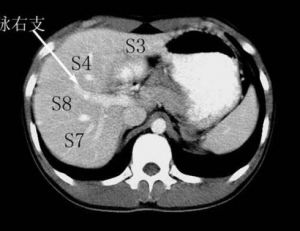

Couinaud根据门脉系统肝段按顺时针方向标以罗马数字从ⅠⅡⅢⅣⅤⅥⅧ,其中左内叶及尾状叶不再分段。 肝脏分8个段,主要被肝静脉系统和门静脉系统分割。肝中静脉将肝分成左右两叶。肝右静脉分肝右叶为右前、右后两部分。肝左静脉分肝左叶为左内叶、左外叶。门静脉系统走行于肝段内。Ⅰ段为尾状叶,CT示在门、腔静脉之间,Ⅱ段(靠上)与Ⅲ段(靠下)构成左外叶,Ⅳ段为方叶,也是左内叶,Ⅴ段(靠下)与Ⅷ(靠上)段构成肝右前叶,Ⅵ段(靠下)与Ⅶ段(靠上)构成肝右后叶。至于Ⅱ段与Ⅲ段、Ⅴ段与Ⅷ段、Ⅵ段与Ⅶ段分界,粗略方法以肝内门静脉分支或肝门平面为分界标志,出现以上平面所显示的是靠上方的,Ⅱ段、Ⅶ段、Ⅷ段,以下层面就是Ⅲ段、Ⅴ段、Ⅵ段。Ⅴ段与Ⅵ段、Ⅶ段与Ⅷ段之间以肝右静脉分界。影像学上横断面上以肝静脉为界,2,3;5,8;6,7 的分界大约门静脉左右分支平面。 医学百科网 | YxBaike.Com

1、肝脏分段的意义:可以了解病灶所处位置,尤其对于肝脏恶性肿瘤患者,从而指导治疗。肝脏的分段和肝脏的解剖密切相关,了解了肝脏的解剖并且应用到影像学的分析中去,也就可以熟练的了解肝脏的分段了。 2、分段主要依靠CT。 CT:首先找出肝脏的三大静脉:肝中静脉,肝左静脉,肝右静脉;找出门静脉及其分叉部位。门静脉分叉可以区分上段和下段,即肝S5/S8,S6/S7,门静脉分叉以上为S8,S7;肝右静脉和肝中静脉之间是右前叶,肝右静脉以后是右后叶;一般规律,从CT上看,最先看到的是S8,然后是S2、3,肝左外叶以肝裂为界,比较容易辨认,左内叶为肝裂和肝中静脉之间区域,胆囊往下的层次是S5,最后的层面一般是肝S6,下腔静脉和门静脉夹着的是尾状叶,即S1。